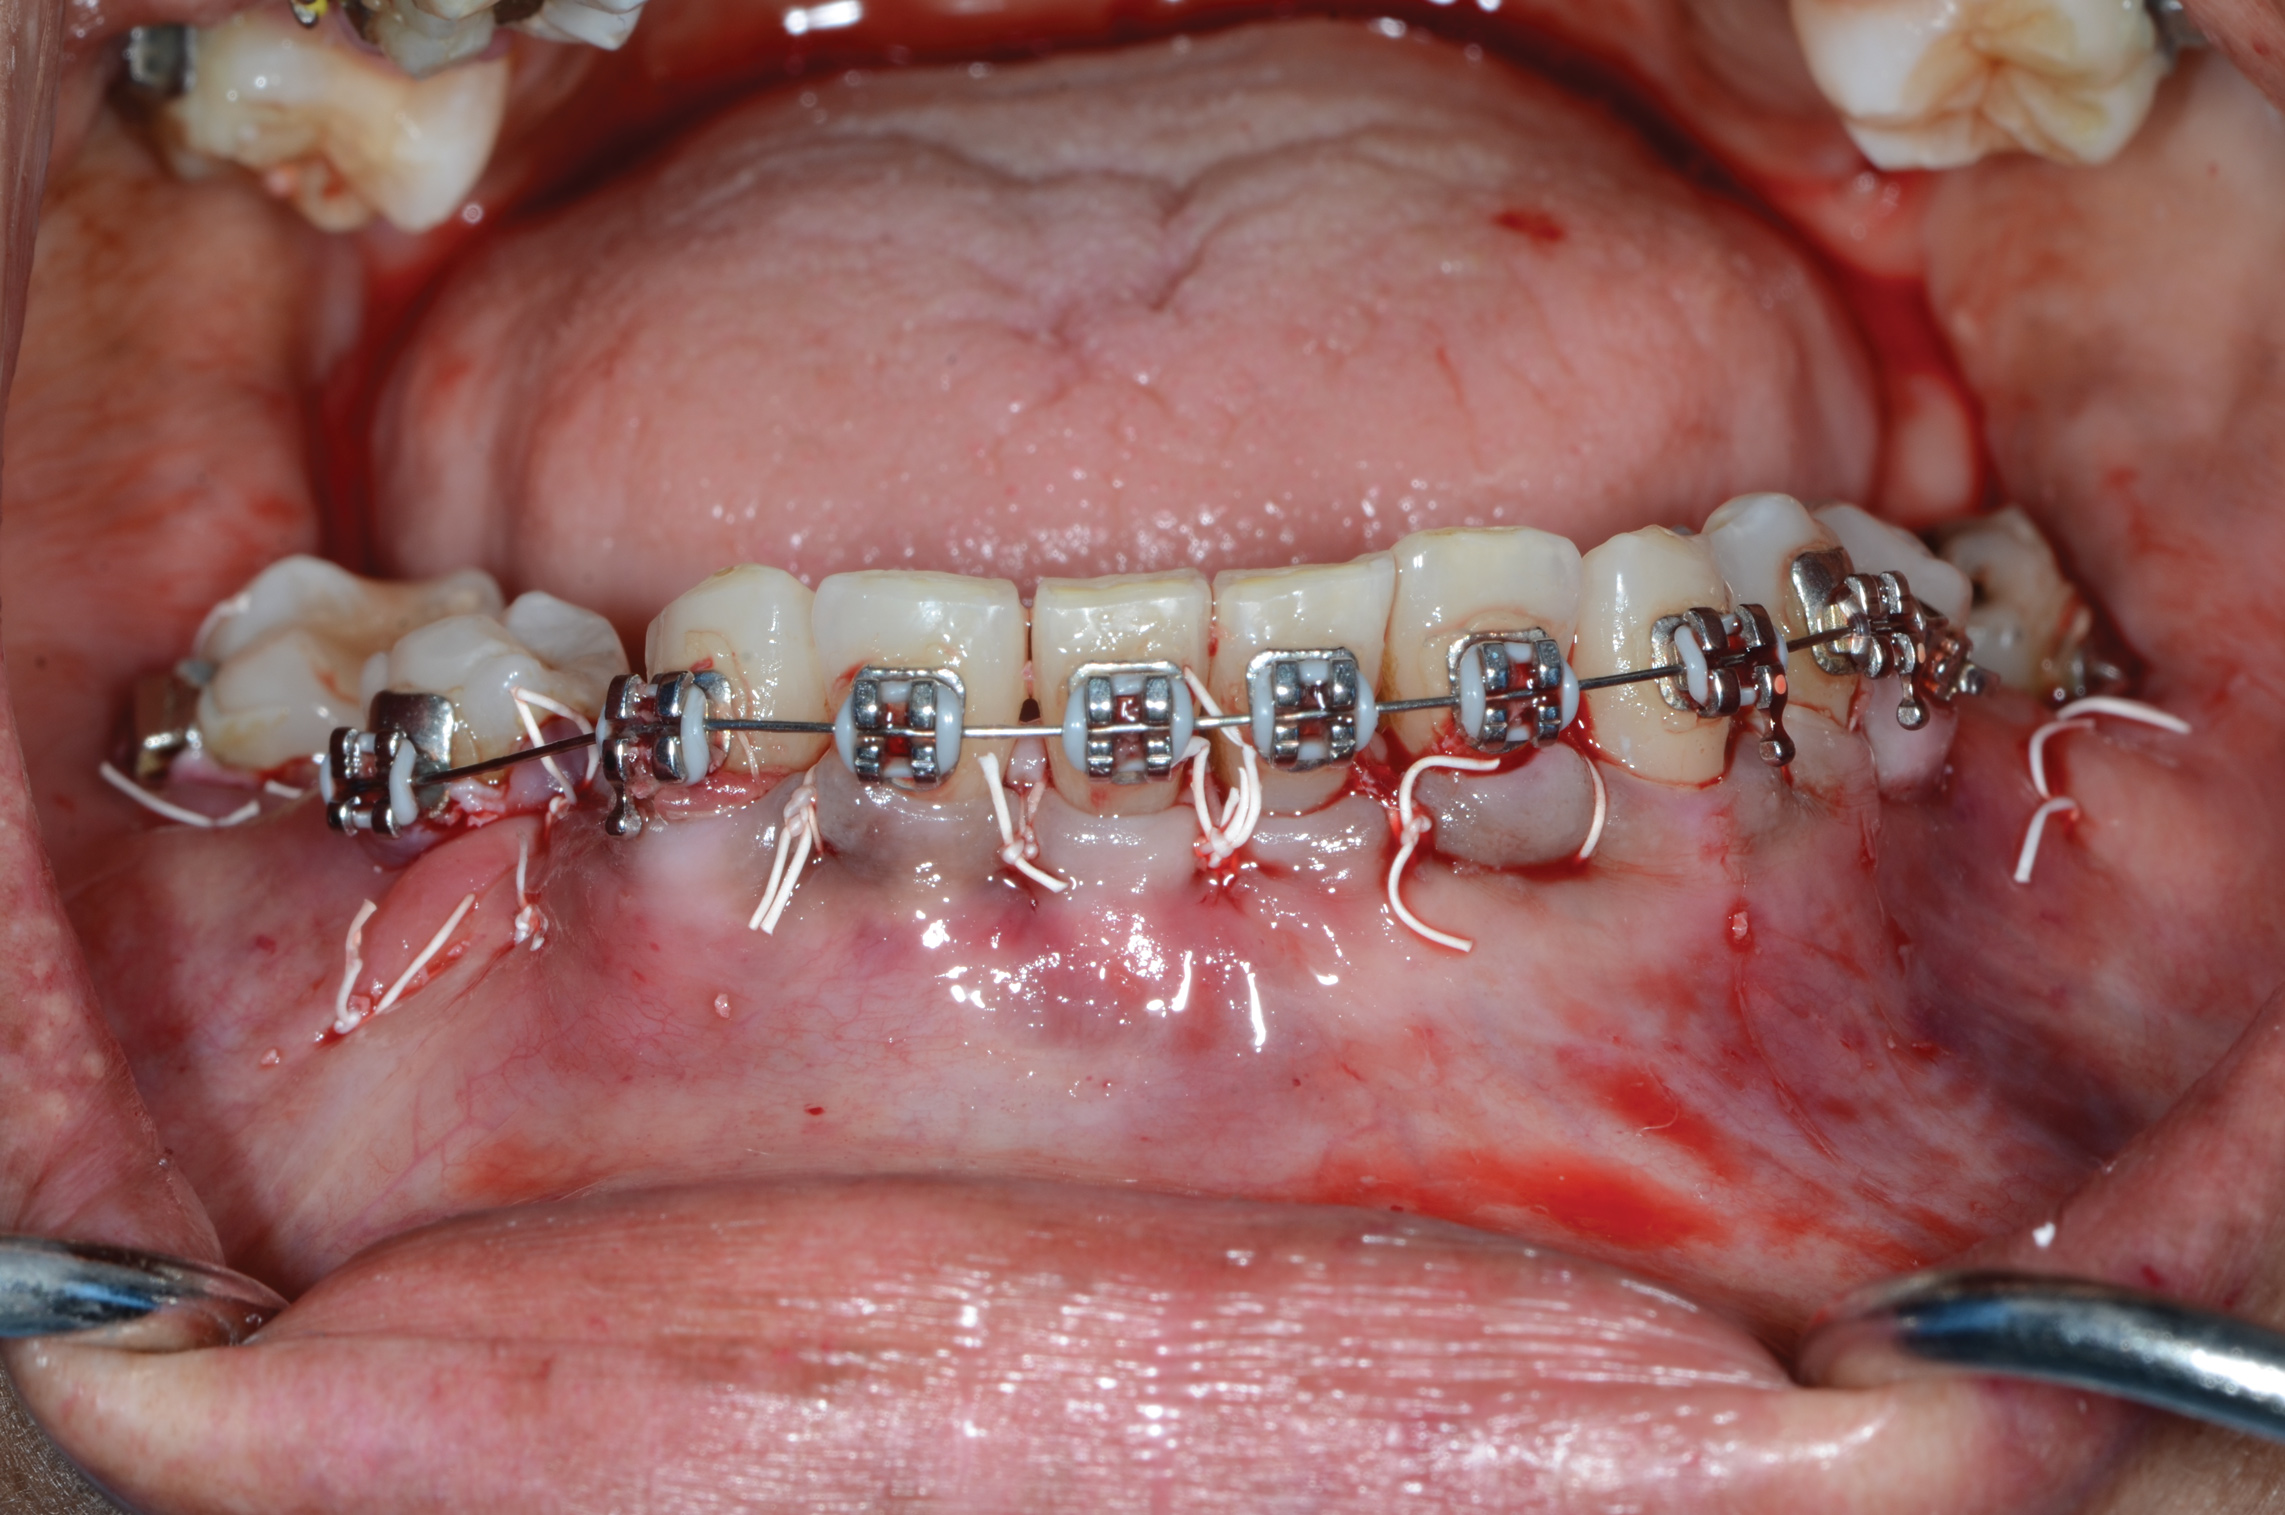

Fig 2. An abundant amount of bone biomaterial was placed during SFOT to compensate for anticipated graft shrinkage during healing.

Figure 2

Fig 3. Suturing after SFOT procedure; note the shallow vestibule post-closure.

Figure 3